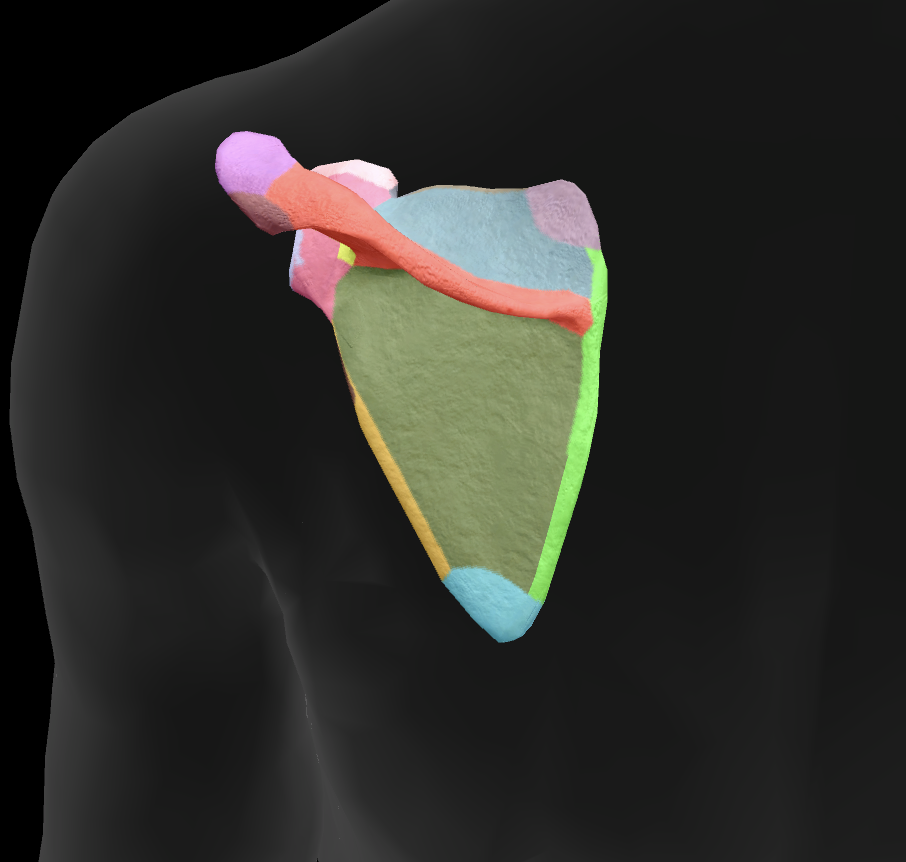

What bone is this?

scapula

What is this boney landmark?

spine of scapula

What is this boney landmark?

supraspinous fossa

What is this boney landmark?

infraspinous fossa

What is this boney landmark?

acromion process

What is this boney landmark?

superior angle

What is this boney landmark?

inferior angle

What is this boney landmark?

lateral border

What is this boney landmark?

medial border

What is this boney landmark?

subscapular fossa

What is this boney landmark?

spinoglenoid notch

What is this boney landmark?

glenoid fossa

What is this boney landmark?

supraglenoid tubercle

What is this boney landmark?

infraglenoid tubercle

What is this boney landmark?

coracoid process